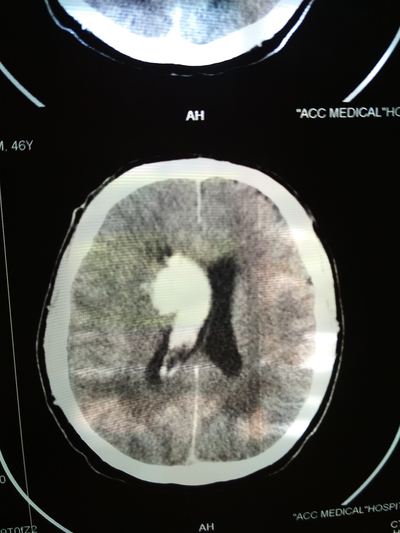

День не помню, возможно 1-2 марта, открываю глаза, а вокруг суета и непонятная обстановка. Осознаю что я а больнице, меня перетягивают с кровати на носилки и куда-то катят и тащат, укрыли сверху одеялом, внесли на улицу, очень холодно. Притащили (по другому не назовешь) меня на компьютерную томографию, перекинули с носилок на стол КТ, голову уложили в ячейку для головы и чем-то расклинили, чтобы не шевелился, больно капец. Я уже осознал что нахожусь в больнице, но что произошло не могу понять, да и думать мне было очень больно в голове.

Вернули меня в палату, перекинули на койку, и мои родные начали рассказывать, что 22 февраля мне стало плохо, качало, тошнило и рвало, жена подумала, что я выпил с друзьями в гараже. Потом вызвали скорую, которая померяла давление и там 290 на 160. Что то укололи. Потом возили в одну в больницу, они отказались принимать, повезли в другую. Вот так с 26 февраля я оказался в "еврейской", это у нас так называют гкб1. (городская клиническая больница № 1) По компьютерной томограмме врач определил геморрагический инсульт и аневризма, вот описание что это такое:

Пример аневризмы сосудов головного мозга

После КТ со мной общался врач, видя, что я уже в сознании, трогал руки ноги, просил потянуть рукой его руку, у меня плохо слушалась правая сторона тела.

Ещё врач сказал что желудочки головного мозга заполнились вытекшей кровью и они решают или вскрывать черепушку или медикаментозно лечить.

Вот тут я пересрал, совершенно не хотел проветривать бестолковку (но обрадовался когда на снимках всё таки обнаружили мозг 😁)